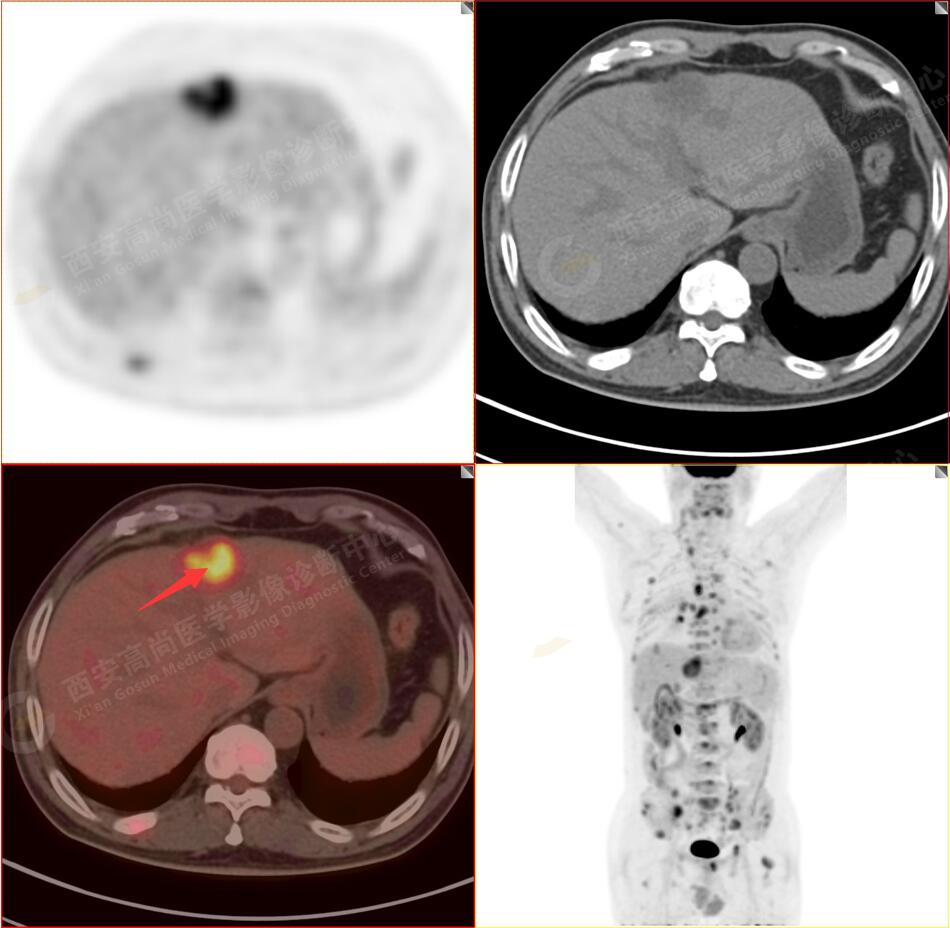

2.以下為全身多發(fā)轉移灶

4.肝S4、8段團塊狀及結節(jié)狀低密度病變,以S4段病變?yōu)橹什煌潭菷DG代謝異常增高,考慮為肝多發(fā)轉移。